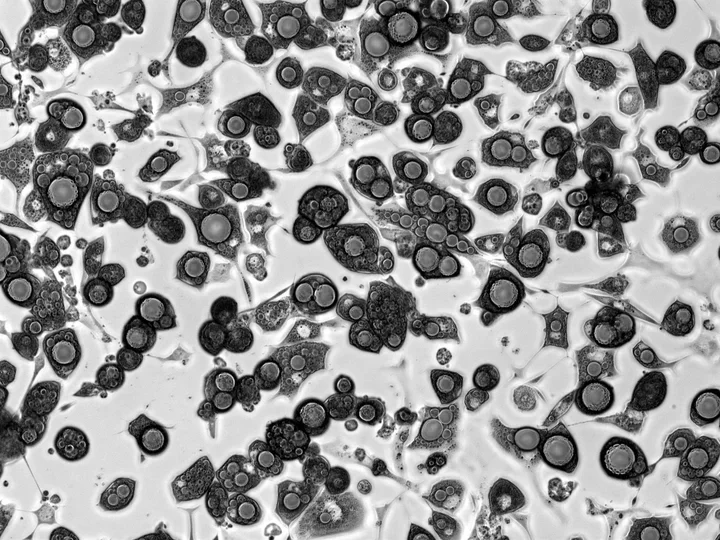

3T3-L1 cells differentiated into mature adipocytes with large lipid droplets.